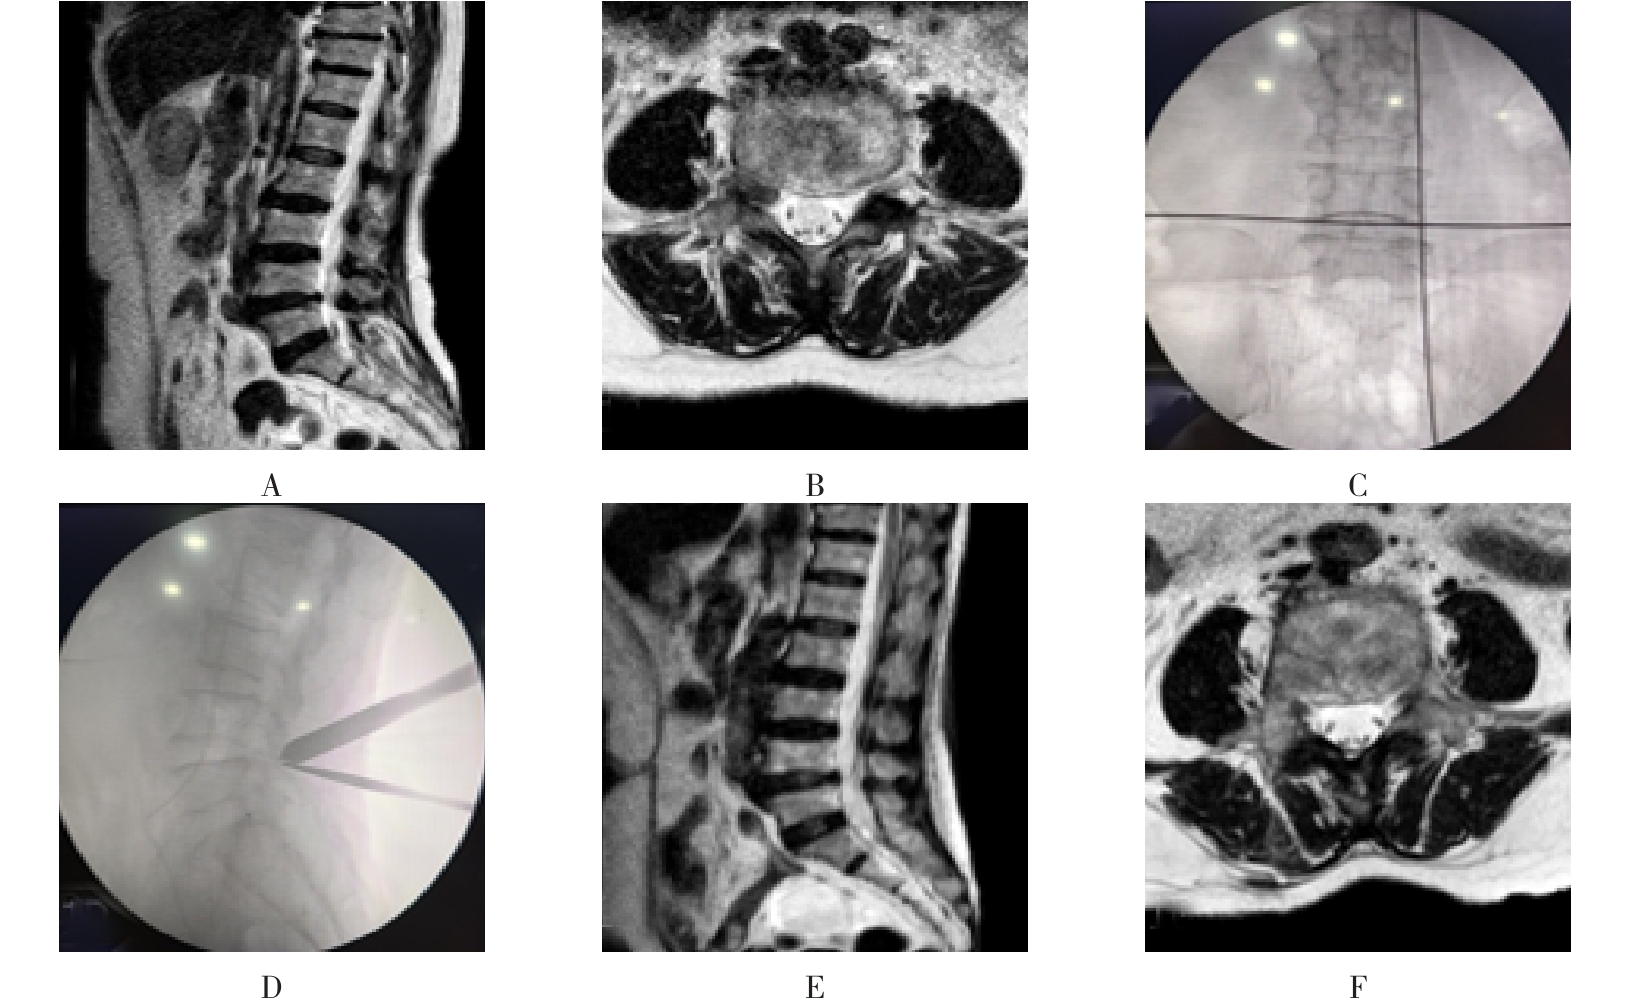

摘要:目的 比较单侧双通道内镜(UBE)与经皮椎间孔镜下髓核摘除术(PTED)治疗极外侧型腰椎间盘突出症(FLLDH)的临床疗效。方法 回顾性分析2021年3月-2023年3月于该院进行治疗的FLLDH患者42例,根据手术方法不同,将患者分为UBE组(18例)和PTED组(24例)。记录并比较两组患者手术时间、术中透视次数、住院时间和围手术期并发症等指标。采用疼痛视觉模拟法(VAS)评估疼痛程度,Oswestry功能障碍指数(ODI)评估功能障碍情况,Macnab评分标准评估临床疗效。结果 UBE组手术时间为(95.56±20.94)min,较PTED组的(78.25±17.23)min长,术中出血量为(69.17±8.95)mL,较PTED组的(23.96±5.89)mL多,差异均有统计学意义(P < 0.05)。UBE组住院时间为(5.67±1.28)d,与PTED组的(5.33±1.05)d比较,差异无统计学意义(P > 0.05)。UBE组术中透视次数为(3.00±0.77)次,明显少于PTED组的(7.42±0.93)次,差异有统计学意义(P < 0.05)。两组患者术后VAS评分和ODI较术前明显降低,差异均有统计学意义(P < 0.05)。术后3 d,UBE组腿痛VAS评分为(3.28±0.58)分及ODI为(41.17±4.30)%,明显低于PTED组的(4.13±0.74)分及(45.50±3.91)%,差异均有统计学意义(P < 0.05),但两组患者术后3个月和1年的VAS评分及ODI比较,差异均无统计学意义(P > 0.05)。两组患者优良率比较,差异无统计学意义(88.9%和87.5%,P = 0.563)。PTED组围手术期出现神经损伤2例,UBE组无神经损伤出现,两组均无感染、复发和大出血等严重并发症发生。结论 PTED与UBE两种手术方式治疗FLLDH均安全和有效。但UBE术中透视次数少,镜下视野更加清晰,神经损伤风险更小。